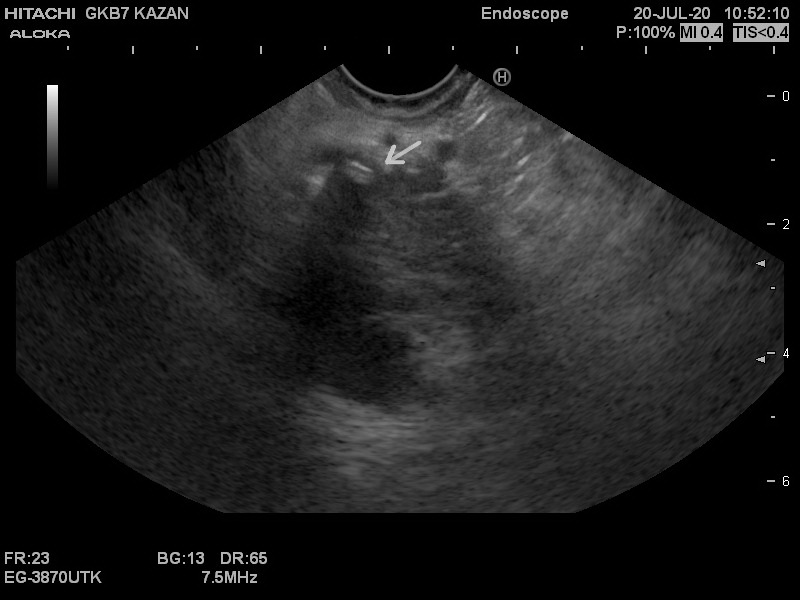

Молодой мужчина именно с такими признаками в экстренном порядке оказался сегодня на операционном столе. Камень, размером 6 мм, перекрывший желчный проток, стал причиной желтухи. Благодаря возможности проведения эндоскопического узи в условиях клиники, данный камень был найден в кратчайшие сроки и удален малоинвазивным эндоскопическим способом, что позволило избежать обширной операции и способствует скорейшему выздоровлению пациента.